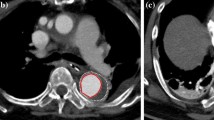

A total of 3 pigs were used in this experiment. The characteristics of the pigs and the size of type A SG were listed in Table 1. All three pigs were male, and their mean weight was 75 ± 5 kg. Before the BRIDGE system was implanted, angiography showed that thoracic aorta and abdominal aorta were normal without any damage in three pigs (Fig. 3a, d). The acute procedure success rate was 100%(3/3). The Acute procedural success was defined in that both the type A and type B SGs were deployed in the appropriate location (while with patency of the supra-aortic trunk and the coronary artery), and successful withdrawal of the delivery system. Angiography immediately after the procedure demonstrated that both the type A and type C SGs were positioned in the appropriate location with the patency of the coronary arteries, the supra-aortic trunk and the significant visceral vessel in the other pigs. No endoleak was revealed by the angiography (Fig. 3b, e).

Among the 3 pigs enrolled in this study, 3 pigs were sacrificed at 3-month after the procedure. The living habits, weight, and diet of all the pigs did not change significantly before the sacrifice. Angiography was performed on the pigs before sacrifice. Angiography 1-month after the procedure showed that type A and type C SGs were positioned in the satisfactory location in the three pigs, with the patency of the coronary arteries, the supra-aortic trunk and the significant visceral vessel. No endoleak, migration or deterioration of the SGs were observed in the angiography. Additionally, no aortoclasia, aortic aneurysm and aortic dissection can be revealed around the SGs by the angiography, indicating the excellent safety of the novel device (Fig. 3c, f).